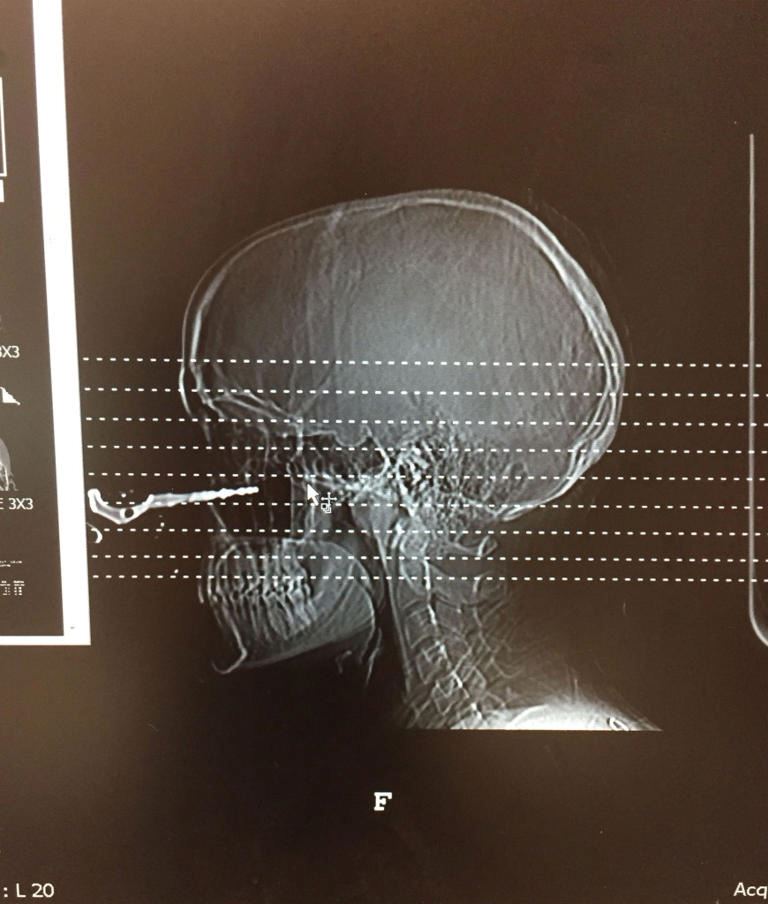

Renee kemudiannya dikejarkan ke hospital dan segera menjalani pembedahan bagi mengeluarkan kunci tersebut.

“Doktor daripada pelbagai jabatan datang melihat saya kerana mereka seakan tidak percaya ia boleh berlaku.

“Ada antara doktor itu yang meminta kebenaran untuk mengambil gambar saya bagi berkongsi kepada pelajarnya bahawa segalanya boleh terjadi,” kata Renee.